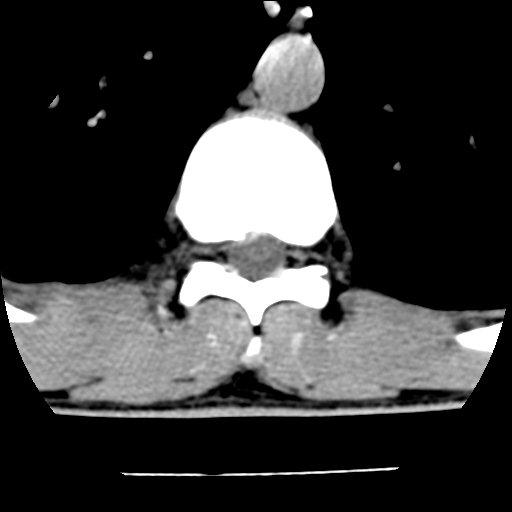

男,31岁,从6米高处坠落伤两天,腰背部疼痛,临床要求ct扫描胸10-腰1。请大家帮忙看看骨质有问题吗?

t12、l1锥体前缘轻度楔形变,平扫示椎体前缘骨小梁欠规整,第9幅图示椎体前缘骨质不连续,结合外伤史考虑椎体轻度压缩骨折。

楼主扫描层厚可能较大,每个椎体只有三个层面.

从所示层面分析,无明确骨折征象,象类似病人我个人会建议mri除外骨挫伤.

从上查骨窗第九片椎体前缘皮质显示断裂.压缩骨折?